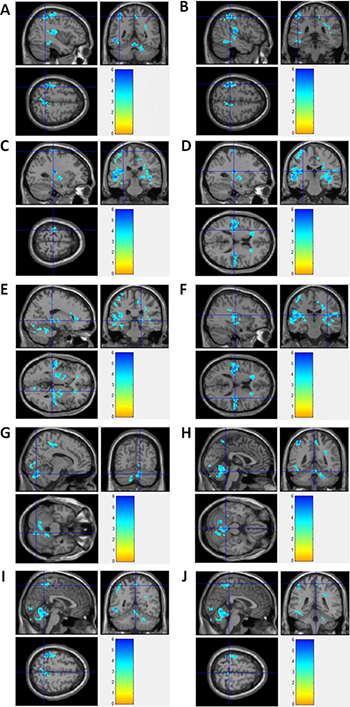

By using resting state BOLD-fMRI scan and ReHo analysis, no increased ReHo region was detected in this study. Instead, we found that the decreased ReHo regions covered left inferior parietal lobule/pre- and post-central gyrus, right thalamus/paracentral lobule/cerebellum anteriorand posterior Lobe, bilateral insula in epilepsy patients, compared to healthy controls (Figure 3). Detailed information for the decreased ReHo regions in epilepsy patients was described in Table 3. Supplementary Figure 2 showed the 3-dimension projection images for decreased ReHo regions in epilepsy patients, compared with healthy controls. Figure 3 showed the sagitta, coronal and axisal plane of the 3-D projection of ReHo map.

Figure 3: fMRI imagines for brain regions with decreased ReHo in epilepsy patients. (A) Left Inferior Parietal Lobule; (B) Left PostcentralGyrus; (C) Left PrecentralGyrus; (D) Left Insula; (E) Right Thalamus; (F) Right Insula; (G) Right Cerebellum Posterior Lobe; (H) Right Cerebellum Anterior Lobe; (I) Right Precuneus; (J) Right Paracentral Lobule.